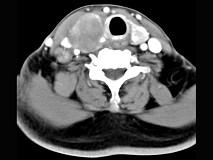

问题 女性,54岁,右侧颈部肿大近1年,近来病人有声嘶、吞咽困难,CT扫描如图,请选择正确的描述和答案()

选项 A.右侧甲状腺肿大,密度减低 B.增强扫描示甲状腺呈不规则强化团块影,其内有低密度区,病灶境界不清 C.右侧颈内静脉增粗,其内可见不规则充盈缺损区 D.考虑甲状腺癌 E.右侧颈内静脉瘤栓形成

答案 ABCDE